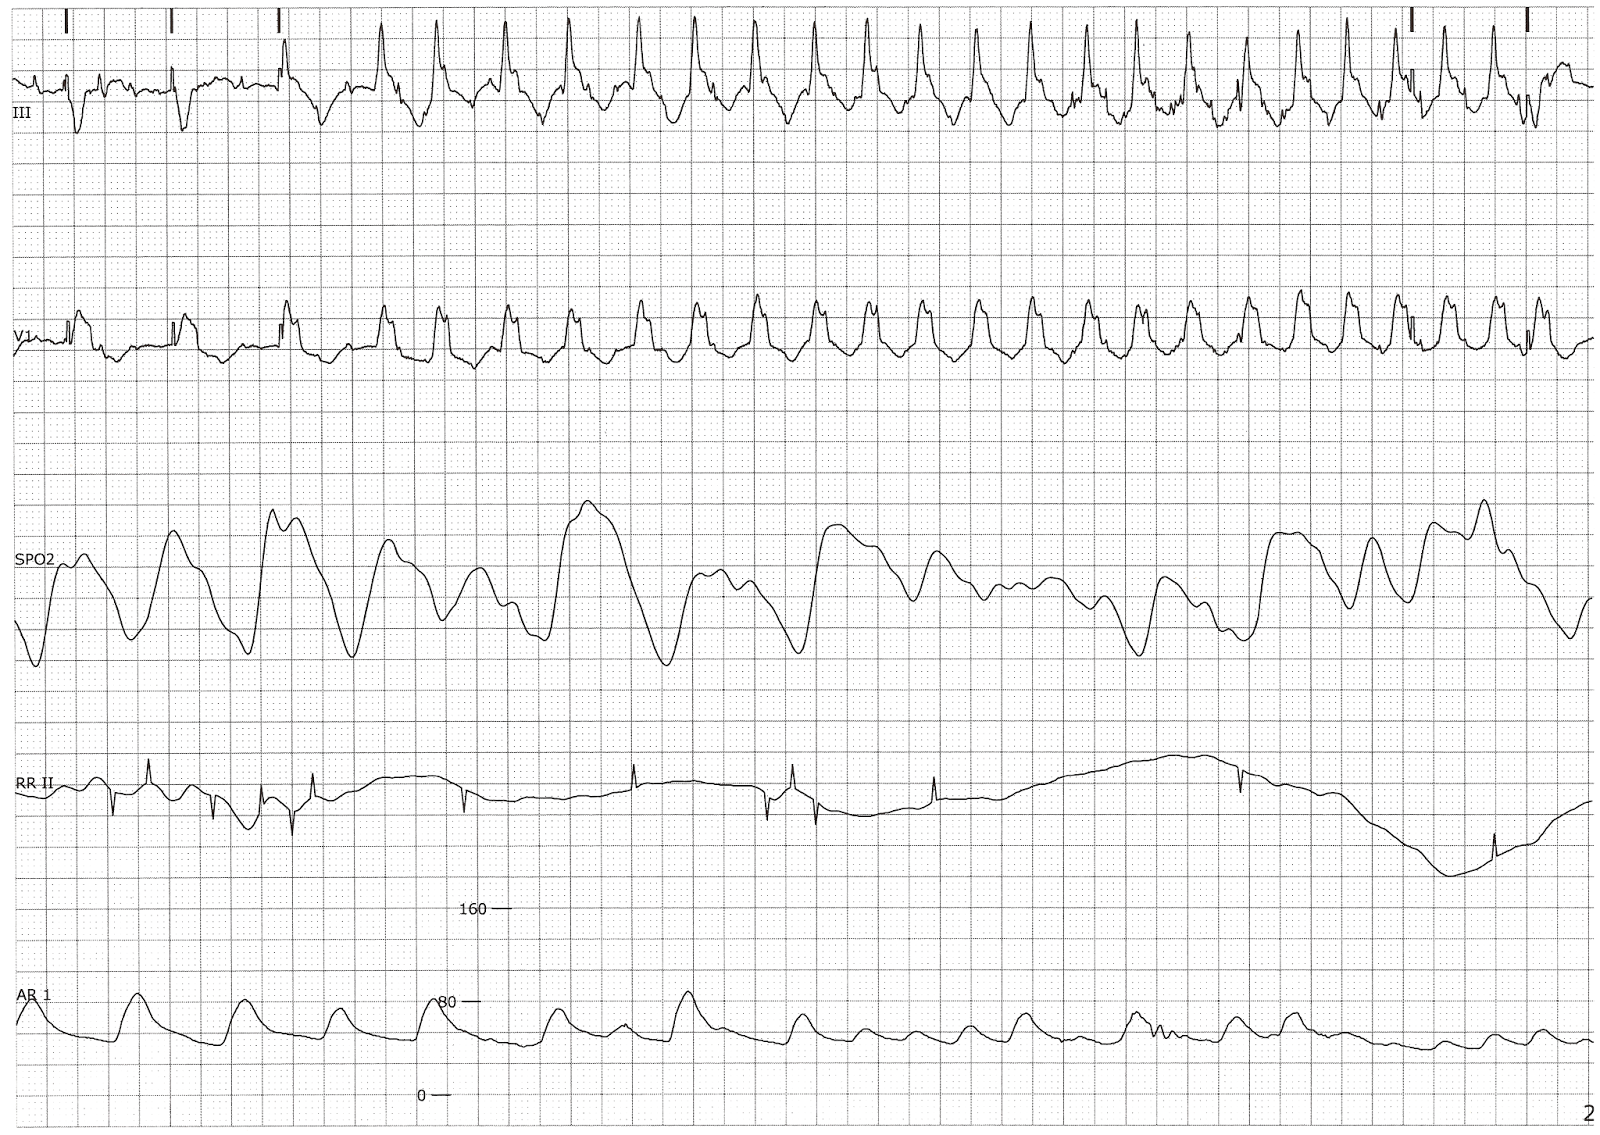

From floatnurse-mike.blogspot.com

Ventricular Tachycardia with a Significant Drop in the Arterial Blood Blood Transfusion Tachycardia fever (temperature of ≥38 o c and rise of ≥1 o c from baseline) fnhtr, ahtr, trali, bacterial contamination, can be unrelated to the blood. Blood transfusion is one of the most common procedures in patients in hospital so it is imperative that clinicians are. reactions can occur during the transfusion (acute transfusion reactions) or days to weeks. Blood Transfusion Tachycardia.